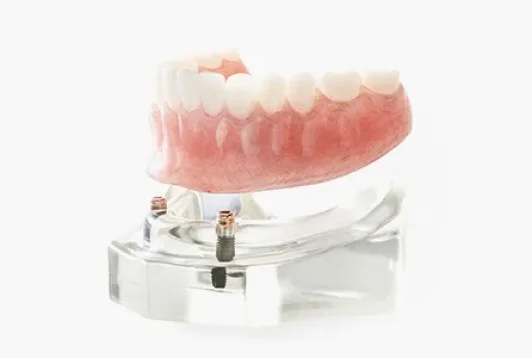

インプラントオーバーデンチャーは 複数の歯を失った方におすすめです

片顎にインプラントを2~6本埋めて土台として、総入れ歯や部分入れ歯を装着する方法をインプラントオーバーデンチャーと言います。通常の入れ歯よりもしっかりとした固定が得られ、かつ全てインプラント治療するよりも費用負担を軽減できます。見た目が自然で取り外し可能な点もこの方法のメリットです。